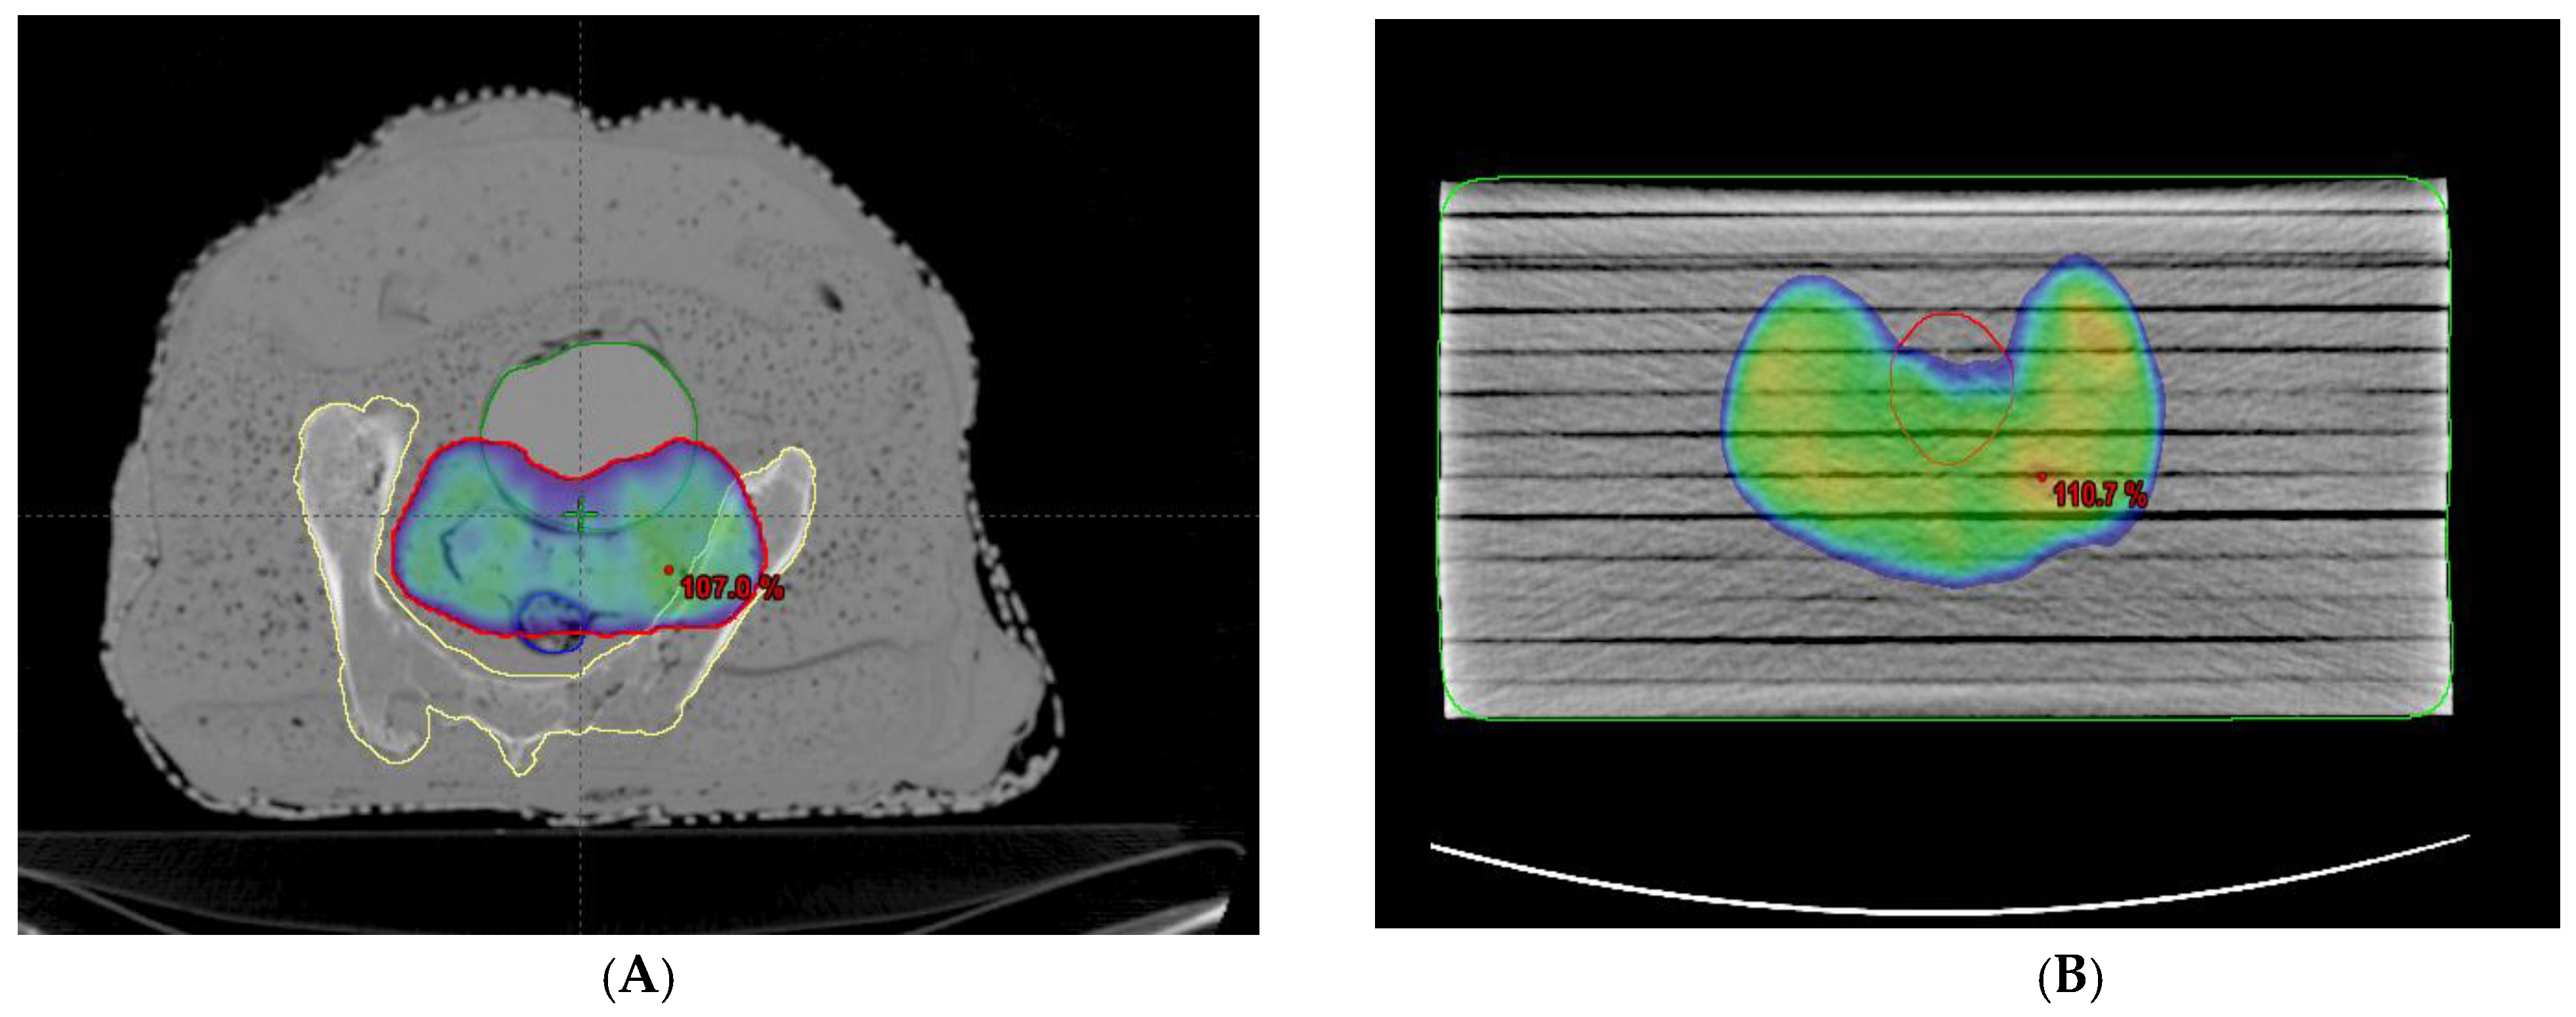

Two kinds of phantoms were chosen for the patient-specific absolute dosimetry of the completed RapidArc treatment plans. The first one was a homogeneous “water-equivalent RW3 solid phantom” (PTW Freiburg, Freiburg, Germany), as shown in Figure 1B, each slab of which was made of polystyrene with the effective atomic number 5.74. The second phantom was the AHFP phantom, as shown in Figure 1A. The density of the internal organs of this AHFP phantom was equivalent to that of the human pelvis. The CT scanning of the phantoms was conducted on a Toshiba Alexion 16 multi-slice CT scanner, with a slice thickness of 2 mm for planning purposes. The CT images were imported into the Eclipse (version 11.0.31) TPS (Varian Medical Systems, Palo Alto, CA, USA), and RapidArc plans already conducted for patient treatment were exported into both phantoms, which can be seen in Figure 3A,B.

Figure 3.

(A,B) RapidArc plan representation on the AHFP phantom and homogeneous (RW3) phantom with dose coverage of 95% of prescribed.